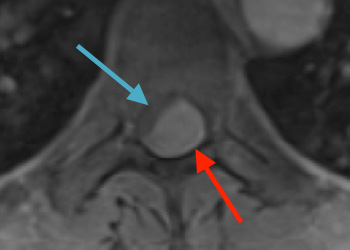

Figure 1: Sagittal post-contrast MRI. Figure 2: Axial post-contrast MRI. Postoperative images looked good (Figure 3). The patient felt better after surgery. His headaches were much […]

Surgery was offered for spinal cord preservation, neurologic preservation, symptomatic management, histopathologic diagnosis, and to decrease the tumor burden. Dr. Gaudin performed an uneventful T7-T9 motion-sparing […]